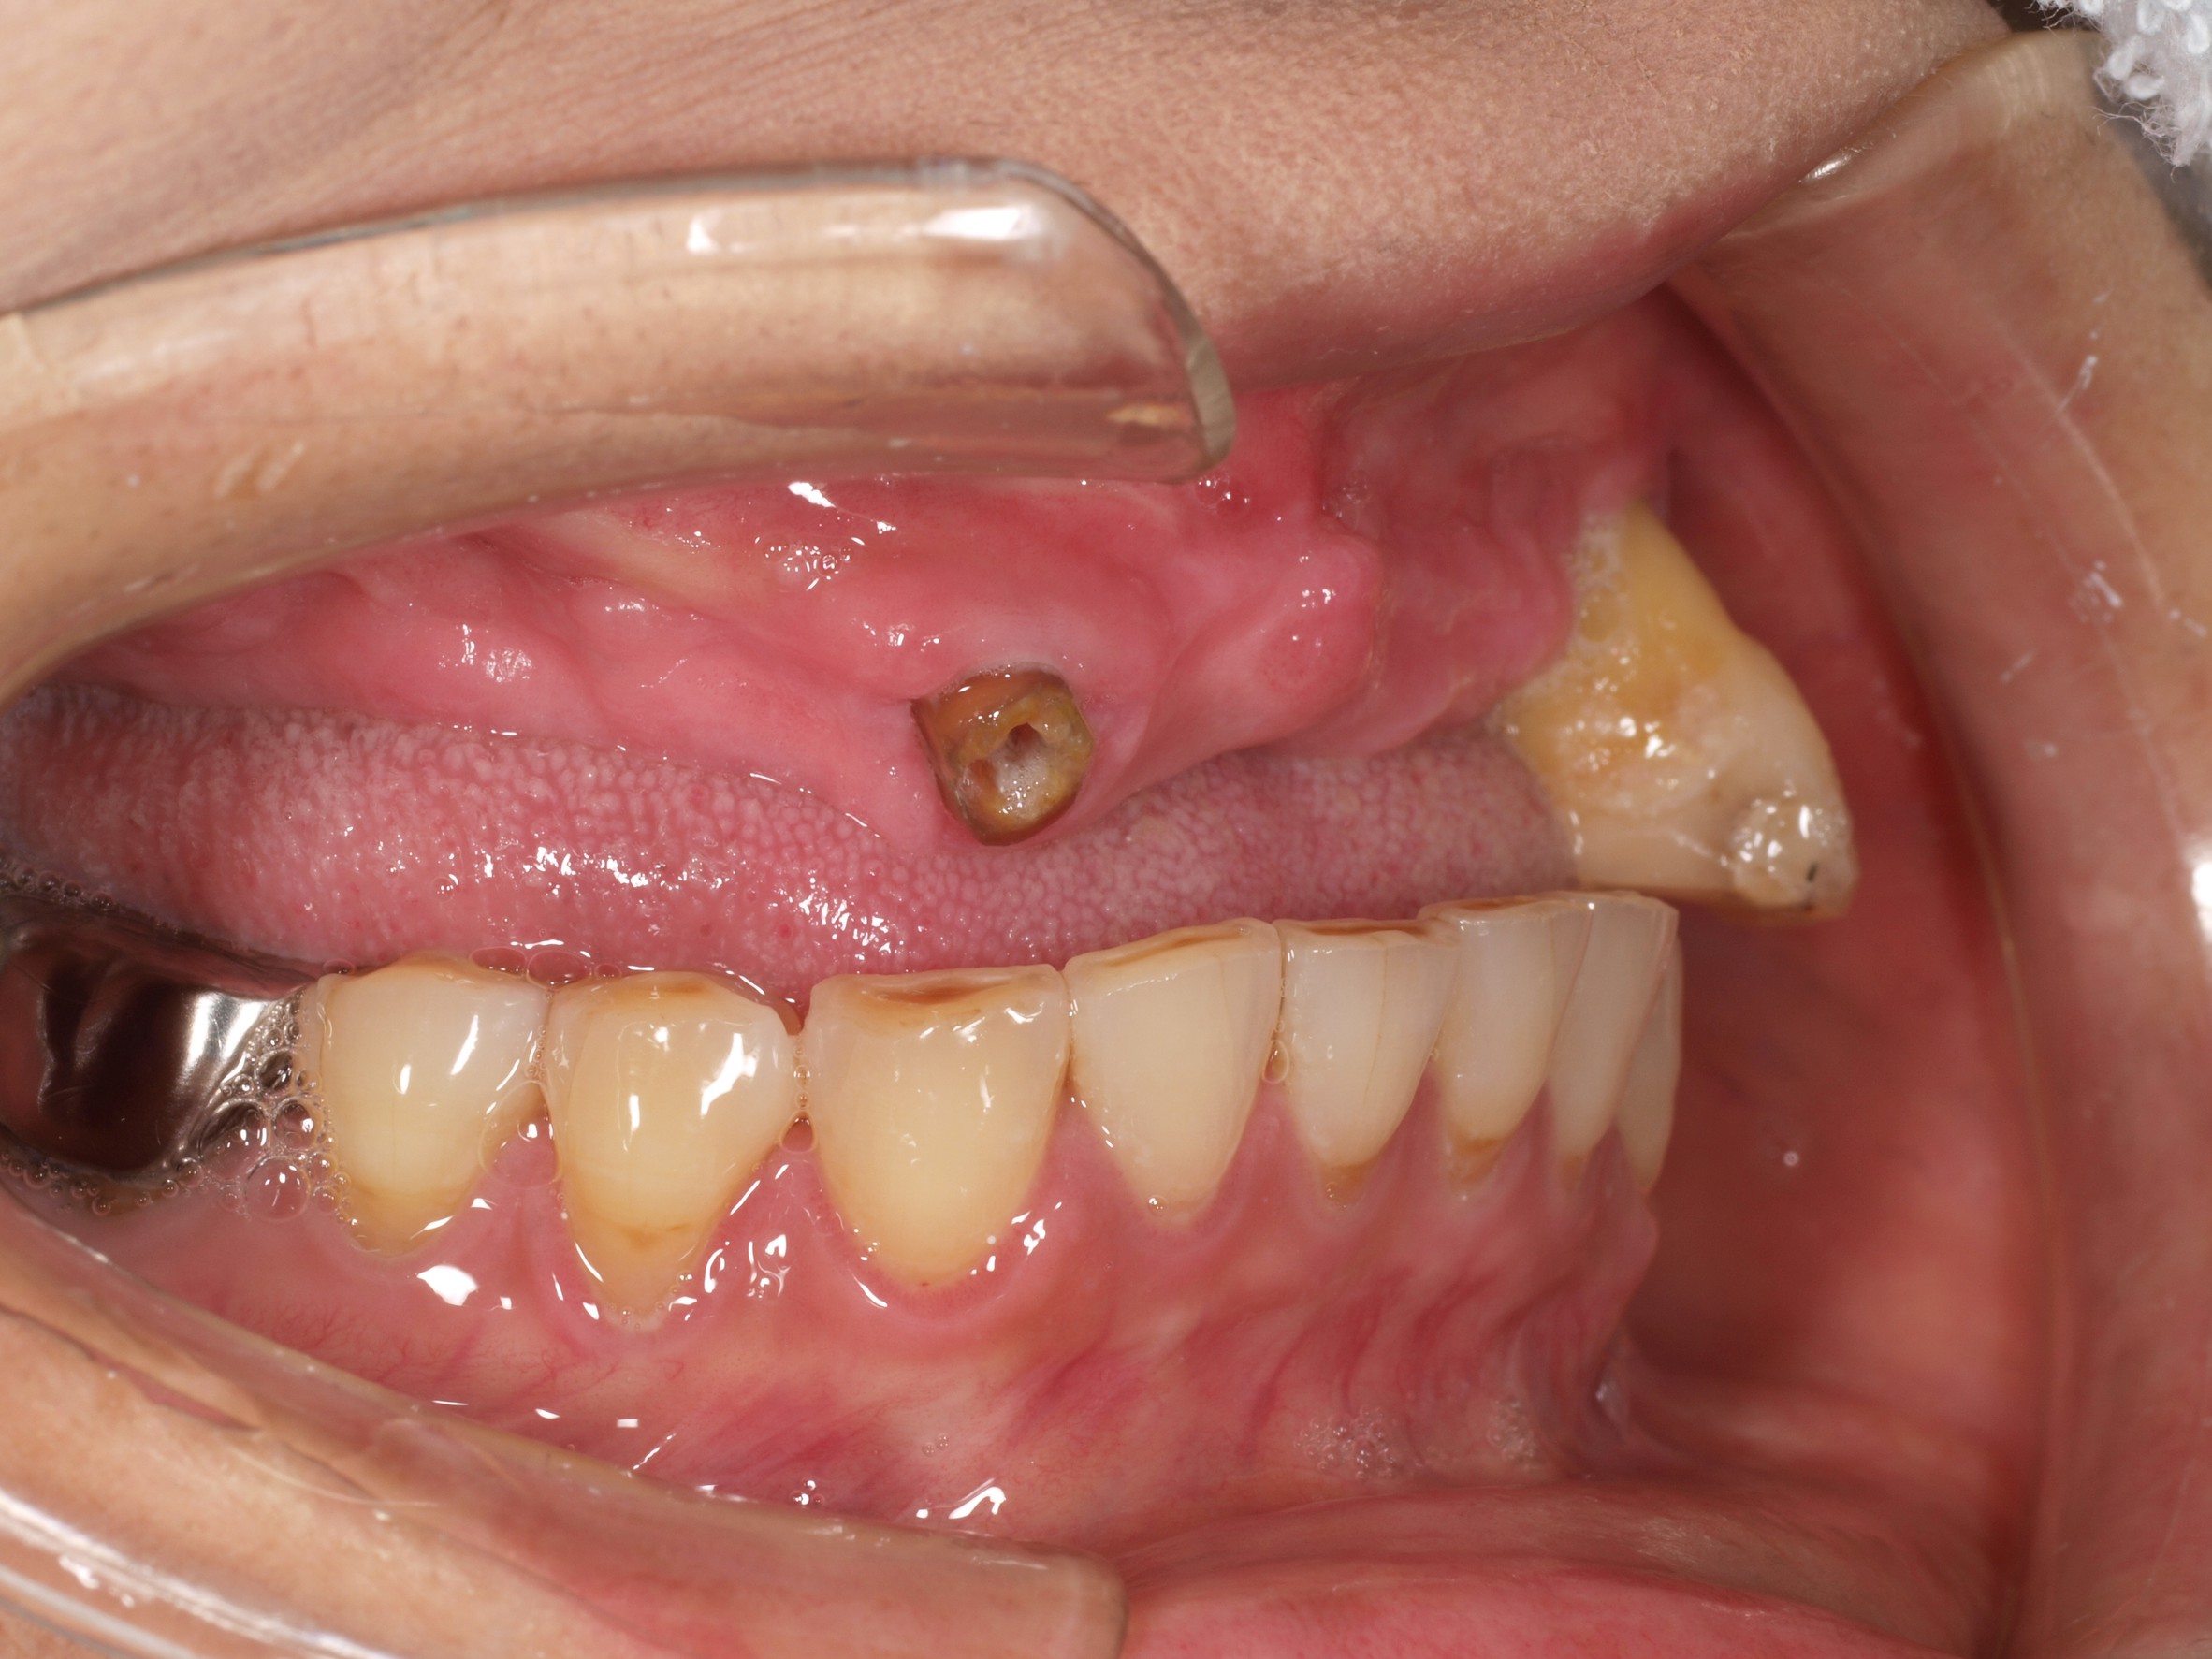

歯周病や虫歯などが原因で、歯がボロボロの状態、歯を失った状態で放置しておくと、歯髄炎や根尖性歯周炎や歯槽膿瘍を引き起こすだけでなく、歯槽骨の吸収も起きるため、最終的には歯を完全に失うことにつながります。また、蜂窩織炎や顎骨骨髄炎などの重大な症状につながることも考えられます。

歯をボロボロの状態にしておくことは、全身への影響も大きく、お口の細菌が、歯茎の血管から全身へ広がり感染症リスクが上昇し、狭心症や心筋梗塞、脳梗塞など発症リスクを高めます。また、歯周病を放置することは糖尿病のリスクを高めるなどの影響もあります。

歯をボロボロの状態にしておくと、さまざまな全身疾患につながるリスクがあるだけでなく、歯を支える骨も徐々に破壊されてしまい、インプラントやオールオン4を入れるための顎骨が残らないケースも少なくありません。

- ・天然の歯がボロボロな状態でありながら、全顎的な歯科治療を必要とされている方

- 主訴

- 入れ歯が気持ち悪く、しっかりと食べれない。本当につらい。美味しく食べて、豊かな人生を過ごしたい。